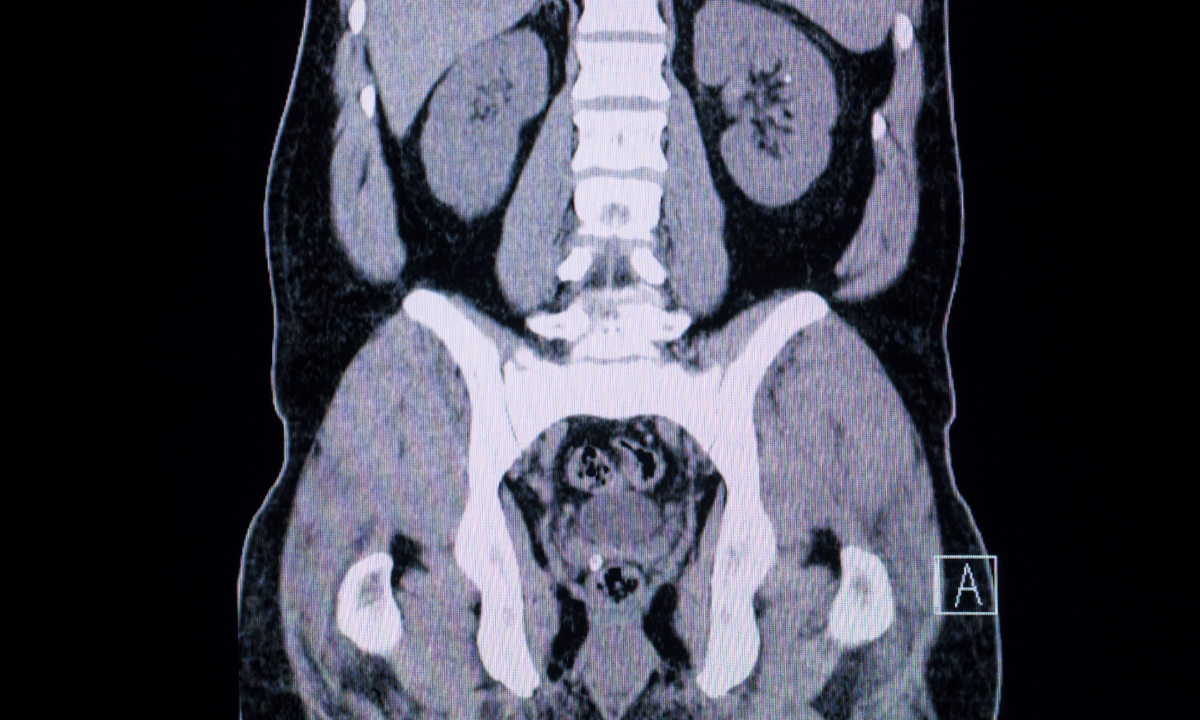

A computed tomography (CT) scan is an advanced imaging test that creates detailed cross-sectional images of your body using X-ray technology and computer processing. Unlike regular X-rays that show just one flat image, a CT scan takes multiple pictures of your abdomen or pelvis from different angles, which gives your doctor a detailed view of your internal structures. This allows your doctor to examine your organs, bones, and soft tissues with clarity, so they can spot abnormal changes that may indicate cancer.

The scan can spot large ovarian tumours, measure their size, and show exactly where they are located in relation to surrounding organs.

It helps determine if cancer has spread to other areas, such as your lymph nodes, liver, intestines, peritoneum (abdominal lining), or other organs.

However, CT scans have significant limitations. Ovarian tumours in early stages are often very small and may not show up clearly on the scan. CT scans are better at detecting larger masses or determining if cancer has spread beyond the ovaries rather than finding early-stage disease. That’s why your doctor will use CT scans in combination with other tests, such as pelvic or transvaginal ultrasounds, CA-125 blood tests, or physical exams, to get more accurate results for diagnosis and staging.